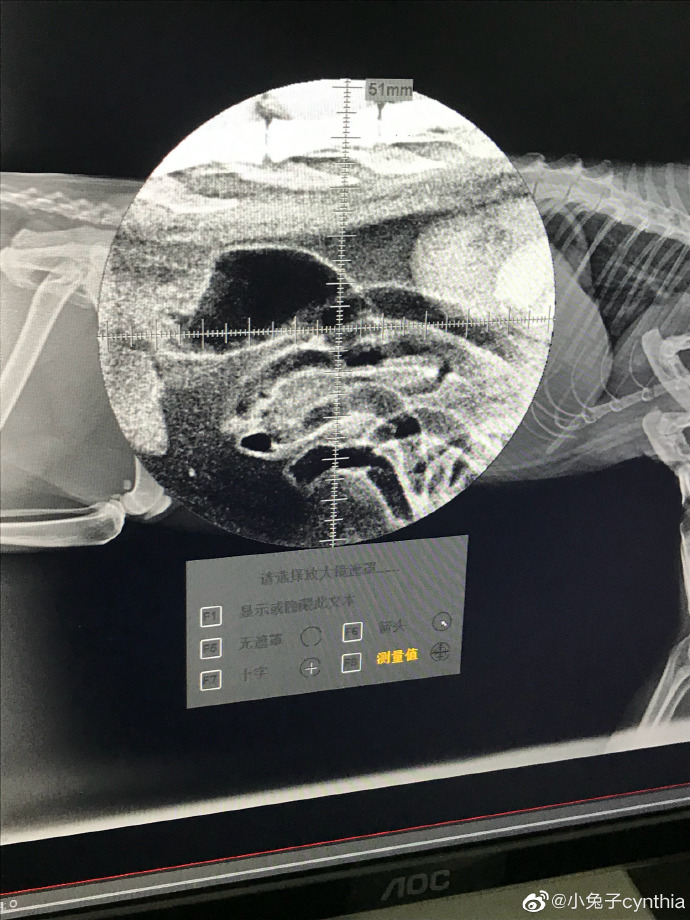

请问猫咪便秘怎么办?已经用过开塞露,猫咪拉了,然后去医院拍了片,医生说肚子里没便便了,开了益生菌,吃了五天,这几天应该没有便便(家里还有一只猫,每天猫砂盆只有一堆便便,以前有两堆),中途喂过一点罐头,但是几天不拉屎不正常,食欲不振,不知道有没有偷偷吃猫粮,求助,谢谢? ...